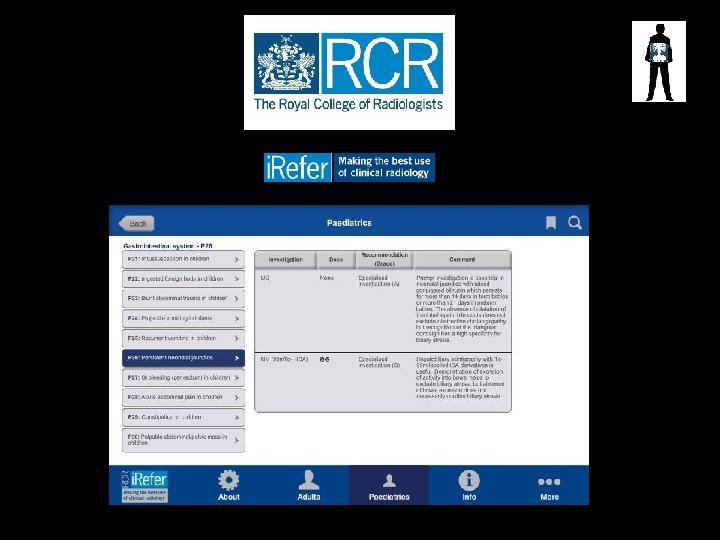

Guidelines for Referral • Royal College of Radiologists (RCR) – “Making the best use of Clinical Radiology” or i. Refer RCR i. Refer guidelines for plain abdominal radiography; Clinical suspicion of perforation or obstruction Acute exacerbation of inflammatory bowel disease Palpable mass (specific circumstances) not often Constipation (specific circumstances) not often Acute and chronic pancreatitis Sharp/poisonous foreign body Smooth and small foreign body, e. g. , coin (specific circumstances) • Blunt or stab abdominal injury • •